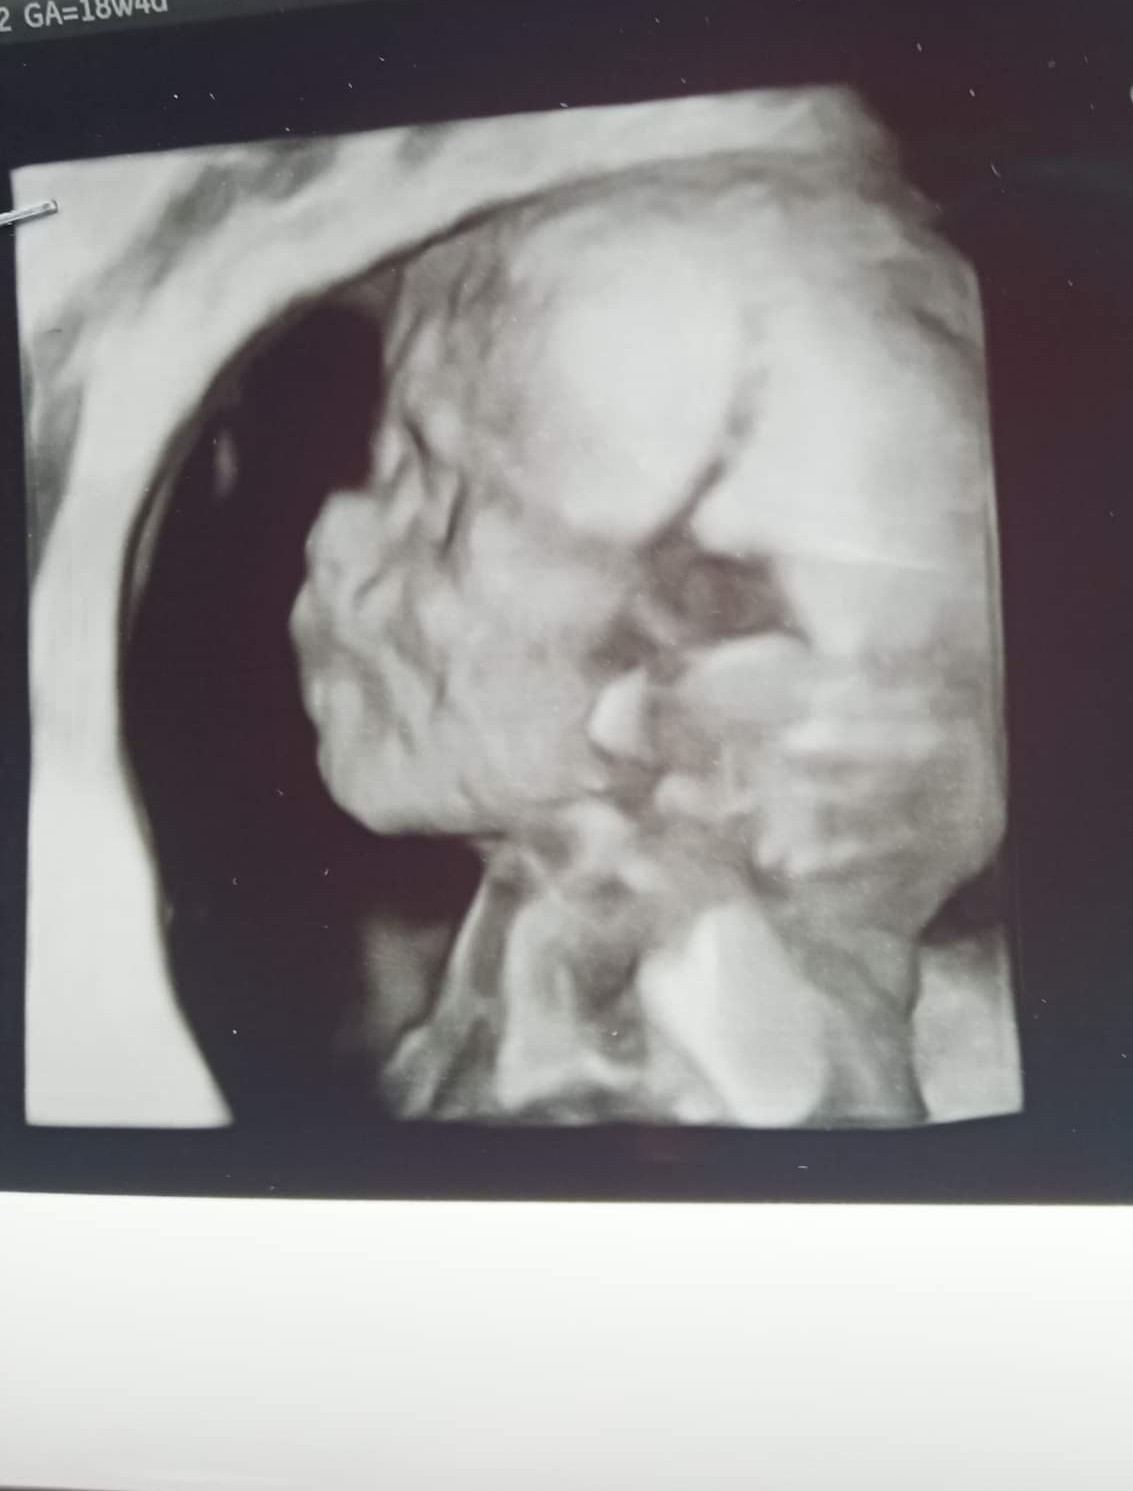

Mam pytanko ,ostatnio w 18 tygodniu robiłam USG i szczeka dziecka wyglądała normalnie a dzisiaj w 19 tygodniu byłam na badaniach prenatalnych i mam wrażenie jakby dziecko miało wysuniętą do przodu górną szczękę.Nie wiem czy po prostu zrobiło taką minę czy coś jest nie tak .Któraś z Was tak miała a dziecko po urodzeniu miało normalną szczękę ?Oba zdjęcia załączam i proszę o odpowiedź.

To nie górna szczęka jest wysunięta tylko żuchwa jest cofnięta - stan fizjologiczny u wszystkich noworodków. Od 6 miesiąca po narodzinach zacznie się powoli wysuwać na właściwe miejsce.